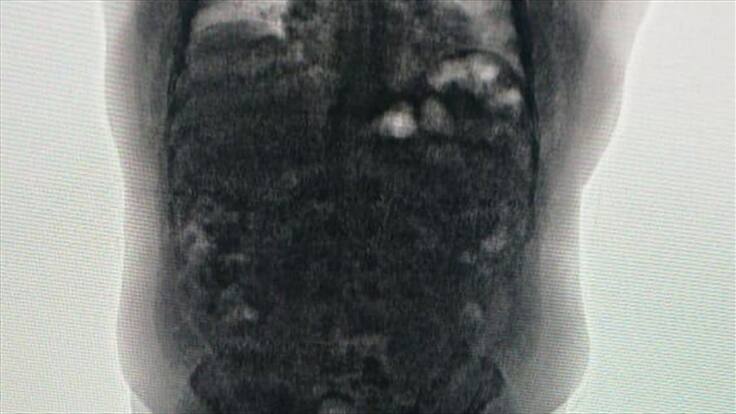

En la valoración realizada a estas dos personas por parte de las autoridades se notó la presencia de cuerpos extraños en sus abdómenes por lo que fueron trasladados inmediatamente hasta el Hospital de Soledad.